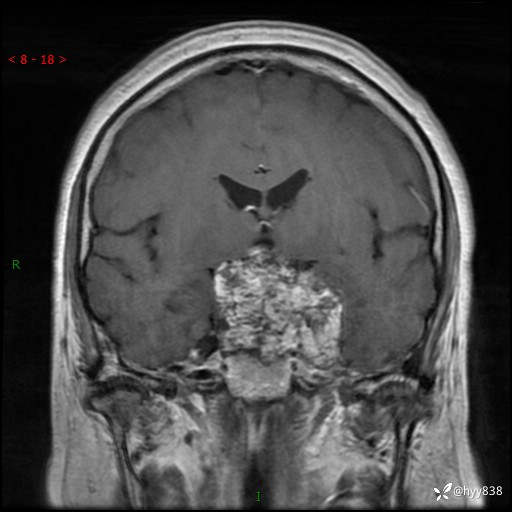

T1WI cor

增强 COR +SAG